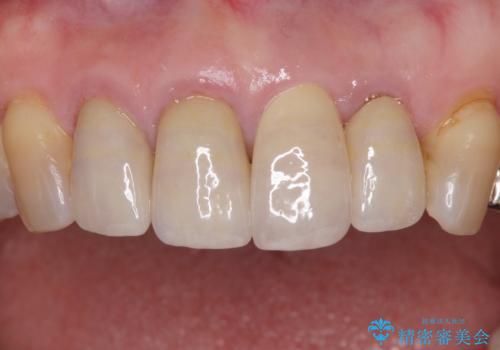

1. 折れてしまった前歯 インプラントによる補綴治療の治療前

3. 折れてしまった前歯 インプラントによる補綴治療の治療後